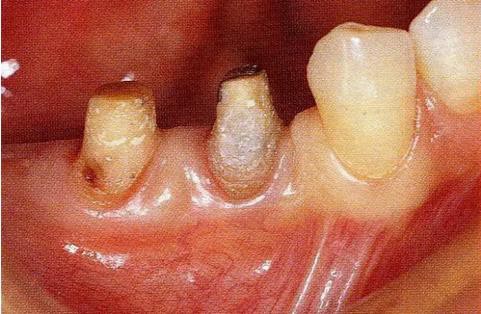

圖17-3   拔牙的同時(shí)做骨外科處理,讓殘留的骨可以盡量平坦化。為了獲得頰側(cè)的附著齦,采用了游離齦瓣的處理。